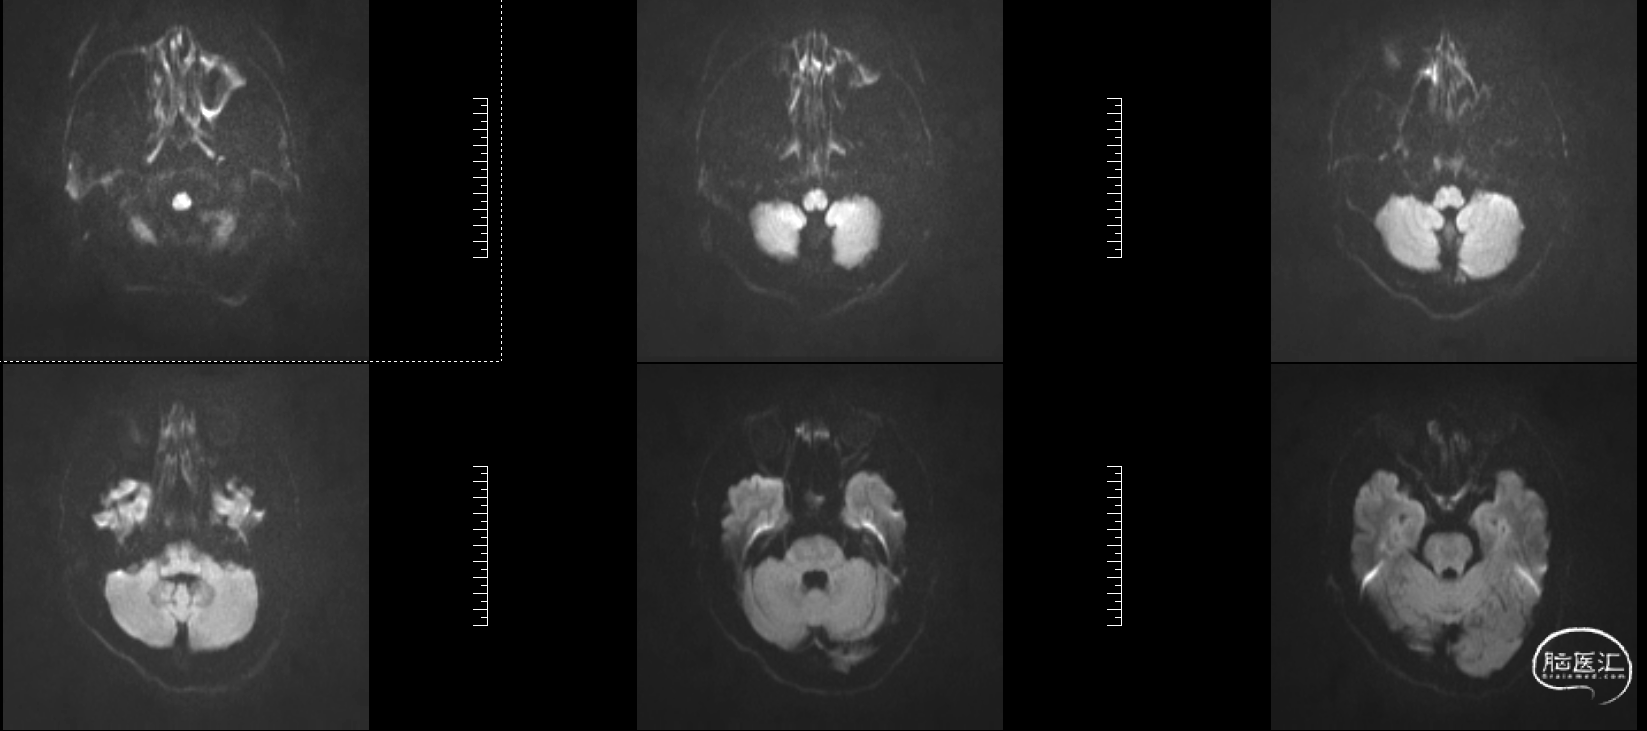

头颅MRI:左侧额顶叶急性脑梗塞;桥脑左份、双侧基底节、右侧脑室旁及双侧额叶多发腔隙性脑梗塞;双侧脑室旁及额顶叶轻度白质脱髓鞘;双侧上颌窦、筛窦、蝶窦炎;脑MRA示①右侧椎动脉纤细(变异)②左侧大脑后动脉P2段局部狭窄③左侧颈内动脉眼段局部严重狭窄④脑动脉轻度硬化改变,请结合临床及其他检查协诊。

溶栓同时急查头颅磁共振DWI。

溶栓同时急查头颅磁共振T2

2、MRI提示:左侧额顶叶急性脑梗塞。